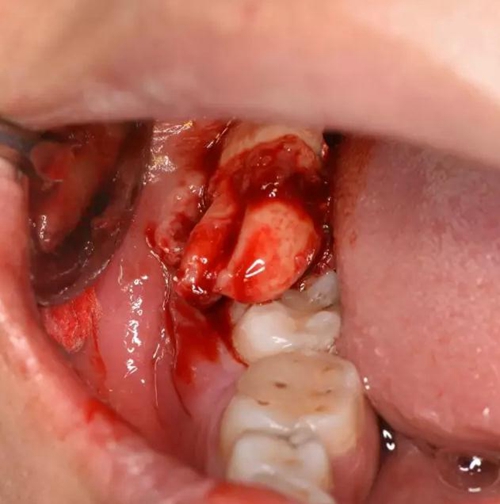

圖6. 剪刀做遠(yuǎn)中小切口、暴露遠(yuǎn)中邊緣嵴

圖7.骨膜剝離器翻開牙齦、暴露48合面

圖8.近中放置牙挺、挺松48

圖9.然后頰側(cè)用挺、挺出48牙齒

圖10.牙齒脫穎而出,48雙根、牙根較大。